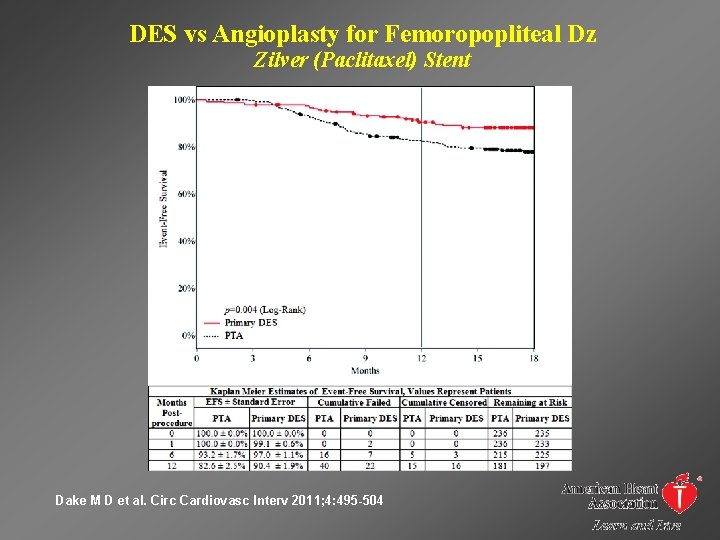

DES vs Angioplasty for Femoropopliteal Dz Zilver (Paclitaxel) Stent Dake M D et al. Circ Cardiovasc Interv 2011; 4: 495 -504